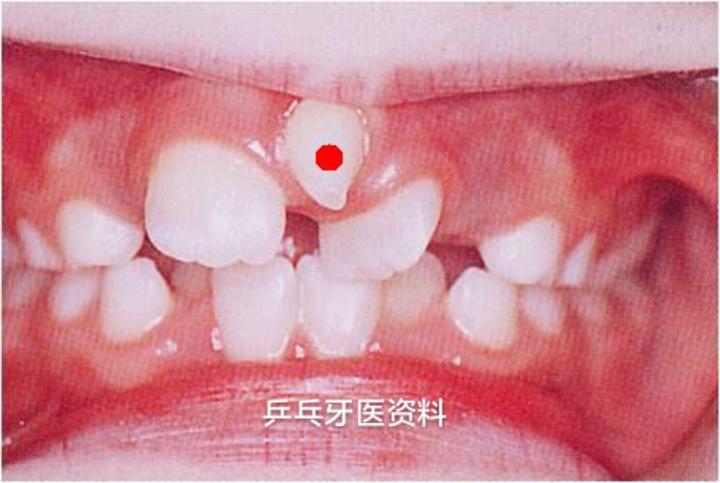

1.门牙间隙过大